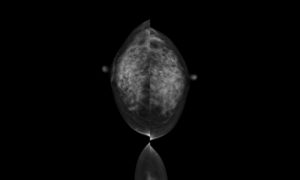

放射線科